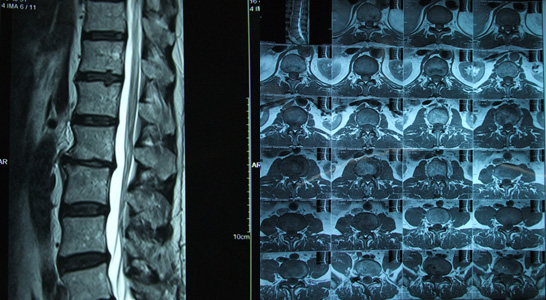

Radiculopatia ciatica L3, mas dolor lumbar irradiado a musculo de miembro inferior.

Dolor region inguinal y debilidad irradiada a musculo de miembro inferior, se coloca espaciador interespinoso en L2-L3 de 14mm 100n, mas foraminectomia y liberacion de raices nerviosas.

Paciente masculino de 53 a, con diagnostico de radiculopatia ciatica l3, mas dolor lumbar irradiado a musculo de miembro inferior, dolor region inguinal y debilidad irradiada a musculo de miembro inferior.

Se coloca espaciador interespinoso en L2-L3 de 14mm 100n, mas foraminectomia y liberacion de raices nerviosas.